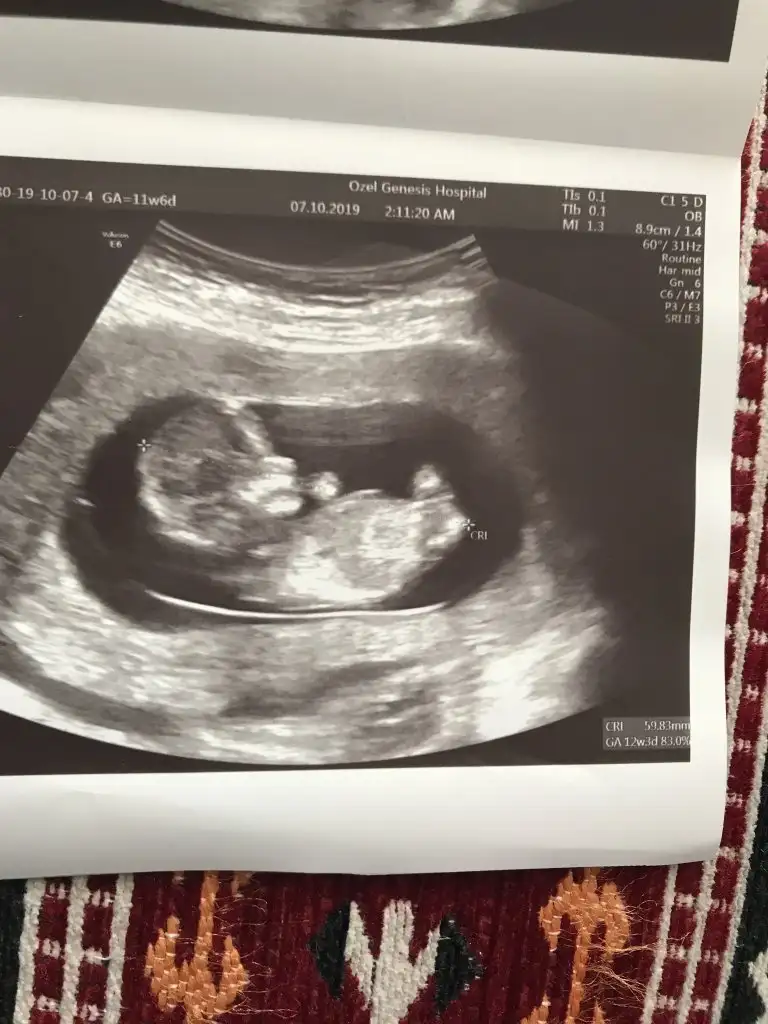

Ikra meyra Ikra meyra 12+3 ultrason görüntüsü cinsiyet tahminini alabilirmiyim canım☺️🤗

• 7BF0D6F6-8A02-4493-A3FD-44DAB8F2DCD2.webp

7BF0D6F6-8A02-4493-A3FD-44DAB8F2DCD2.webp

27,5 KB · Görüntüleme: 57